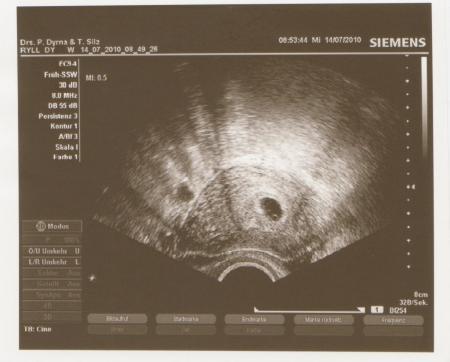

Jetzt kann ich es auch richtig glauben das ich schwanger bin

Das ist so schön das erste Foto in den Händen zu halten

süßes bildchen,ich hoffe morgen auch eins zu kriegen,ich hab morgen eeeeeeeeendlich meinen ersten termin

Ui, das sieht wirklich schön aus - du kannst ja sogar schon dein Krümelchen erkennen....